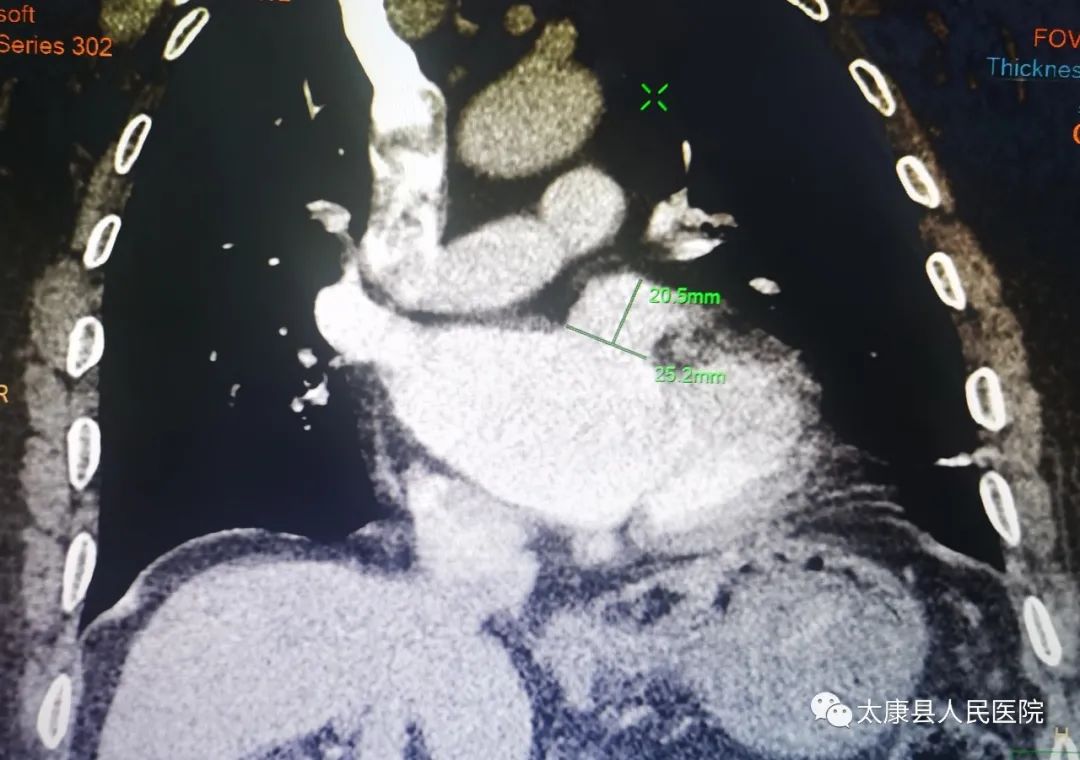

术前完善CTA检查,明确心耳形态及有无血栓

造影显示左心耳呈菜花型

测量心耳开口22mm,深度24mm,选择27mmWATCHMAN左心耳封堵器